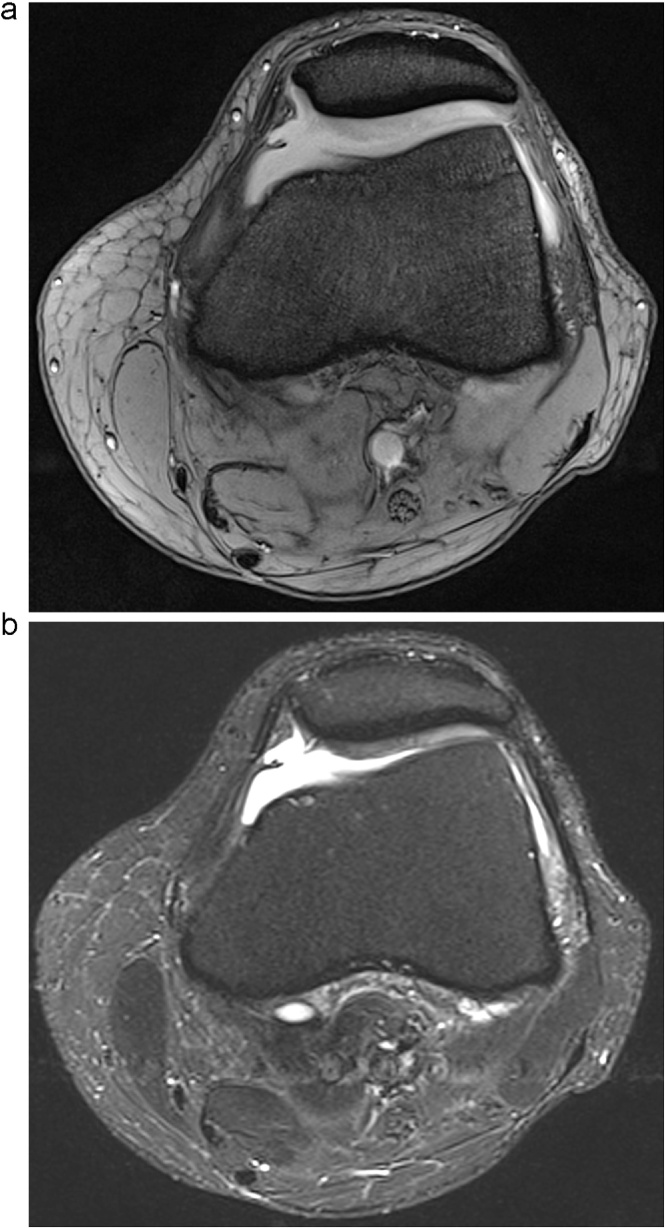

Fig. 1.

Cartilaginous fissure of the medial aspect of the patella imaged with MEDIC (a) and STIR (b). The fissure is presumably caused by a plica mediopatellaris as incision injury. The chondropathia patellae is better depicted by the STIR-sequence (b) due to the higher cartilage-to-effusion contrast-to-noise ratio (STIR = 219 vs. MEDIC = 20).